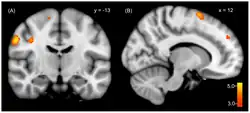

.png)

Mit dem Identitätswechsel gehen Wechsel körperlicher Werte des vegetativen Nervensystems (zum Beispiel Puls, Blutdruck, Muskelspannung, Sehschärfe) und markante Wechsel in der Aktivität des Gehirns einher, wie mit bildgebenden Verfahren wiederholt nachgewiesen wurde.[16][17][18] Auch bestimmte anatomische Abweichungen im Gehirn von Menschen mit DIS wurden wiederholt festgestellt. Diese betrafen jedoch nur statistische Daten von Gruppen, nicht aber die Daten von Einzelpersonen.[19][20]